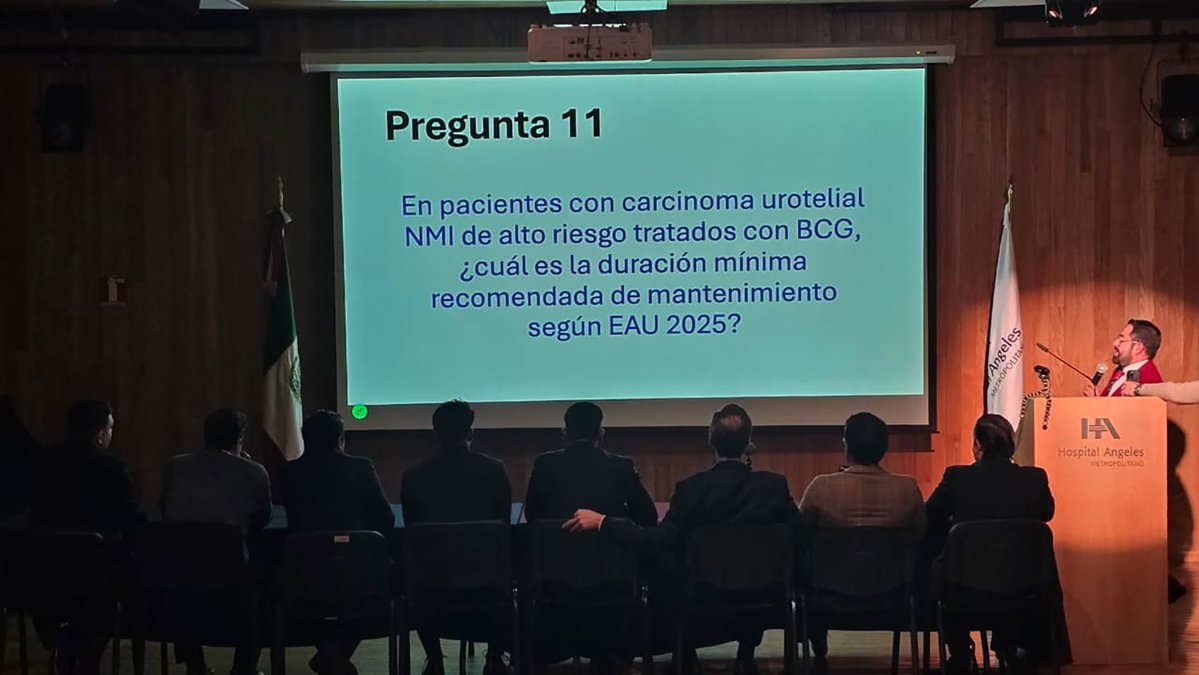

Sesión académica OCTUBRE 2025 👉cmucentro.org #CMUCentro #UrologosCentro #ColegiodeUrologia #urology #SesionesUrologia

Sesión académica OCTUBRE 2025 👉cmucentro.org #CMUCentro #UrologosCentro #ColegiodeUrologia #urology #SesionesUrologia

Sesión académica OCTUBRE 2025, tema central 👉cmucentro.org #CMUCentro #UrologosCentro #ColegiodeUrologia #urology #SesionesUrologia

Sesión académica OCTUBRE 2025, caso clínico 6 👉cmucentro.org #CMUCentro #UrologosCentro #ColegiodeUrologia #urology #SesionesUrologia